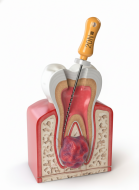

Свищ на десне — это патологический канал, который образуется при воспалении в области корня зуба. Через этот канал организм выводит гной наружу, чтобы снизить внутреннее давление. Появление свища — это знак, что в зубе развивается инфекция, обычно связанная с хроническим воспалением или недолеченным кариесом.

Свищ не исчезает сам по себе — он всегда указывает на скрытую проблему, которую важно лечить у стоматолога.

- Корневой (периапикальный) свищ. Возникает из-за воспаления тканей вокруг корня зуба — чаще всего при запущенном пульпите или гранулёме.

Лечение корневых каналов

- удаление заражённых тканей из канала;

- антисептическая обработка;

- временное пломбирование медикаментами;

- финальная пломбировка канала.

- резекция верхушки корня;

- удаление кист или гранулём;

- иссечение свищевого хода.

Свищ исчезает быстро — обычно через 2–5 дней после начала терапии.

Гранулёма — это ограниченный воспалительный очаг у верхушки корня зуба, возникающий из-за инфекции в корневом канале. По сути, это защитная реакция организма: вокруг инфекции формируется плотная капсула, чтобы не дать воспалению распространиться. Со временем гранулёма растёт, может превращаться в кисту, вызывать боль, отёк, флюс и даже разрушение кости. Поэтому лечить её нужно как можно раньше.

Диагностика — 3D-снимок или визиография для оценки размера очага.

Анестезия — лечение полностью безболезненно.

Ревизия корневых каналов — удаление инфицированных тканей.

Механическая и медикаментозная обработка каналов — тщательная очистка и дезинфекция.

Закладка противовоспалительных препаратов (при необходимости).

Пломбирование каналов — герметичное закрытие очага.